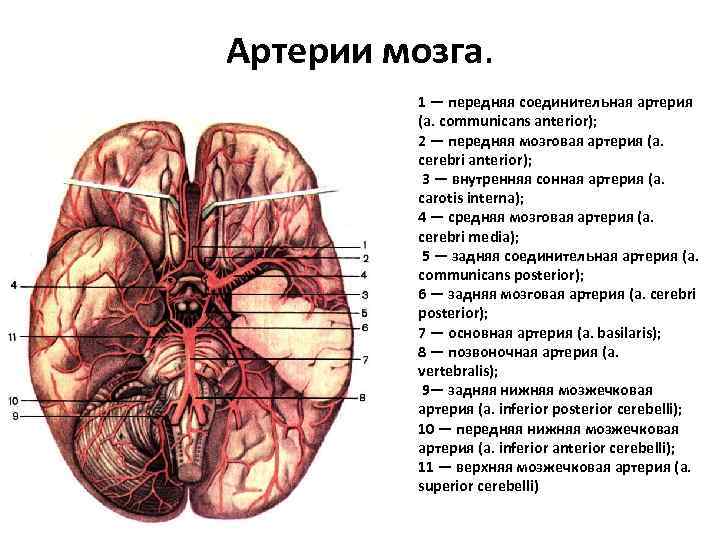

Анатомия: Задняя соединительная артерия мозга